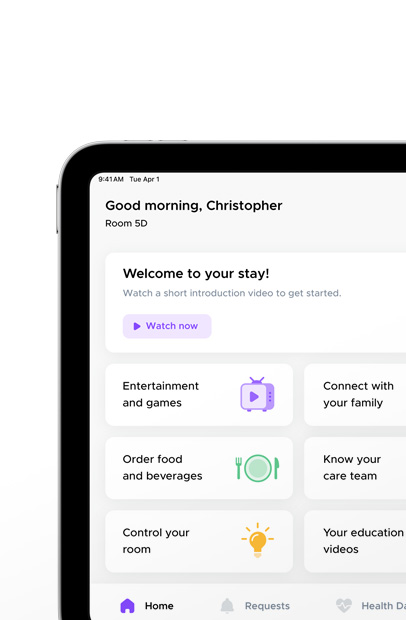

MyChart Bedside makes the in-hospital experience quick and easy for patients. They can message their care team, schedule appointments, see their medication schedule, read health education materials, order food, and

more — right on iPad.